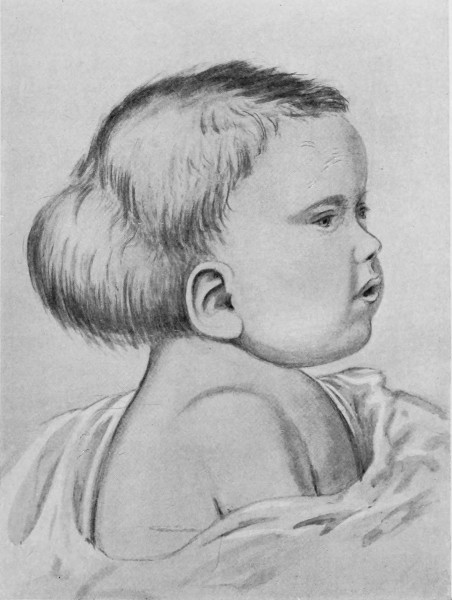

Fig. 21. A Cephalocele over the Anterior Fontanelle.

(For further description, see text.)

3. More rarely, the tumour overlies the anterior or posterior fontanelle. A case of this nature is depicted in Fig. 21, the tumour, situated over the anterior fontanelle, bulging over the temporal and frontal regions to a remarkable extent.

Sincipital cephaloceles are usually quite small, but the occipital variety and those situated in[35] the region of the anterior fontanelle frequently attain a great size (see Figs. 20-22).